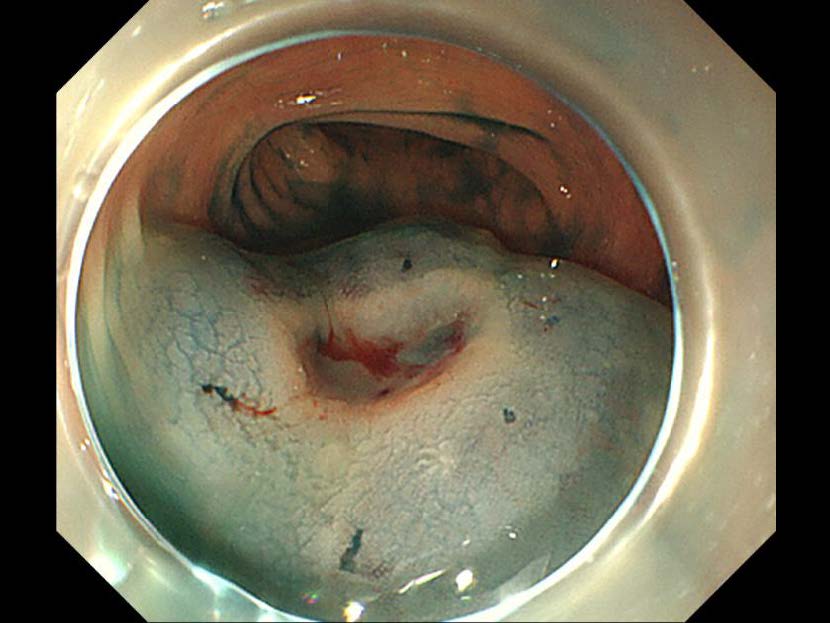

消化管Mapping~大腸~ 2021.10.27

消化器センター 消化器内科

消化管Mapping

消化管Mapping~大腸~

内視鏡検査・治療